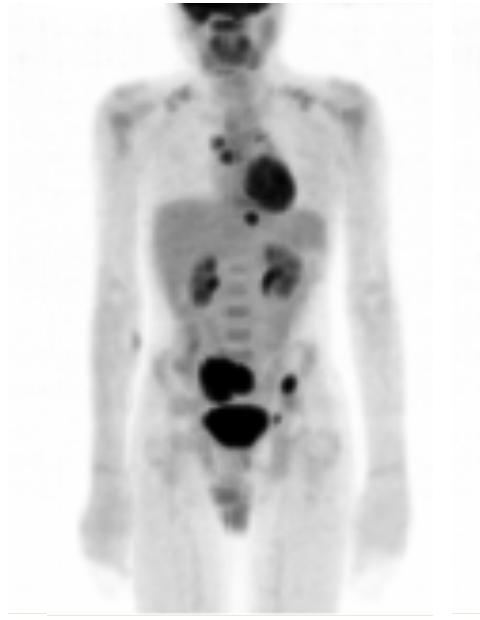

13-year-old male with a sacral mass being evaluated for malignancy and metastasis.

Intense FDG uptake is seen in the right hilar and mediastinal area suspicious for lymph nodes. Focally intense FDG uptake is seen in the region of the upper thoracic spine, lower thoracic spine, left iliac wing and right sacroiliac joint. Mildly intense FDG uptake is also noted in the area left of the bladder. Additionally, there is intense FDG uptake in the known sacral mass.

Intense metabolic activity in the sacral mass is suspicious for malignancy. Abnormal FDG-PET study with hypermetabolic lesions in the regions of the right hilum and mediastinum suspicious for lymph nodes; thoracic spine and pelvis as described above may represent areas of metastasis.

In the context of the sacral mass biopsy on the following day showing numerous non-caseating granulomas with positive acid fast stains consistent with Mycobacterium tuberculosis, the lesions described could represent hypermetabolism due to an infectious/inflammatory process.